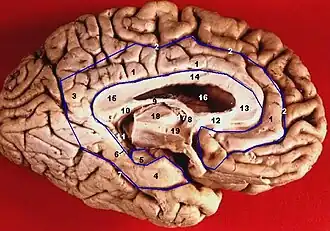

![]() The structures of the Papez circuit in the brain form a curved shape around the brainstem | |

The Papez circuit involves various structures of the brain. It begins and ends with the hippocampus (or the hippocampal formation). Fiber dissection indicates that the average size of the circuit is 350 millimeters. The Papez circuit goes through the following neural pathways:

- Hippocampal formation (subiculum) → fornix → mammillary bodies → mammillothalamic tract → anterior thalamic nucleus → cingulum → entorhinal cortex → hippocampal formation.[4]

A photograph of the inferior medial view of the brain when dissected clearly shows the layout of the Papez circuit. Due to the location of the structures in the circuit, the resulting shape is a limbus. This is what drove MacLean to call the circuit the limbic system when he later modified the circuit.